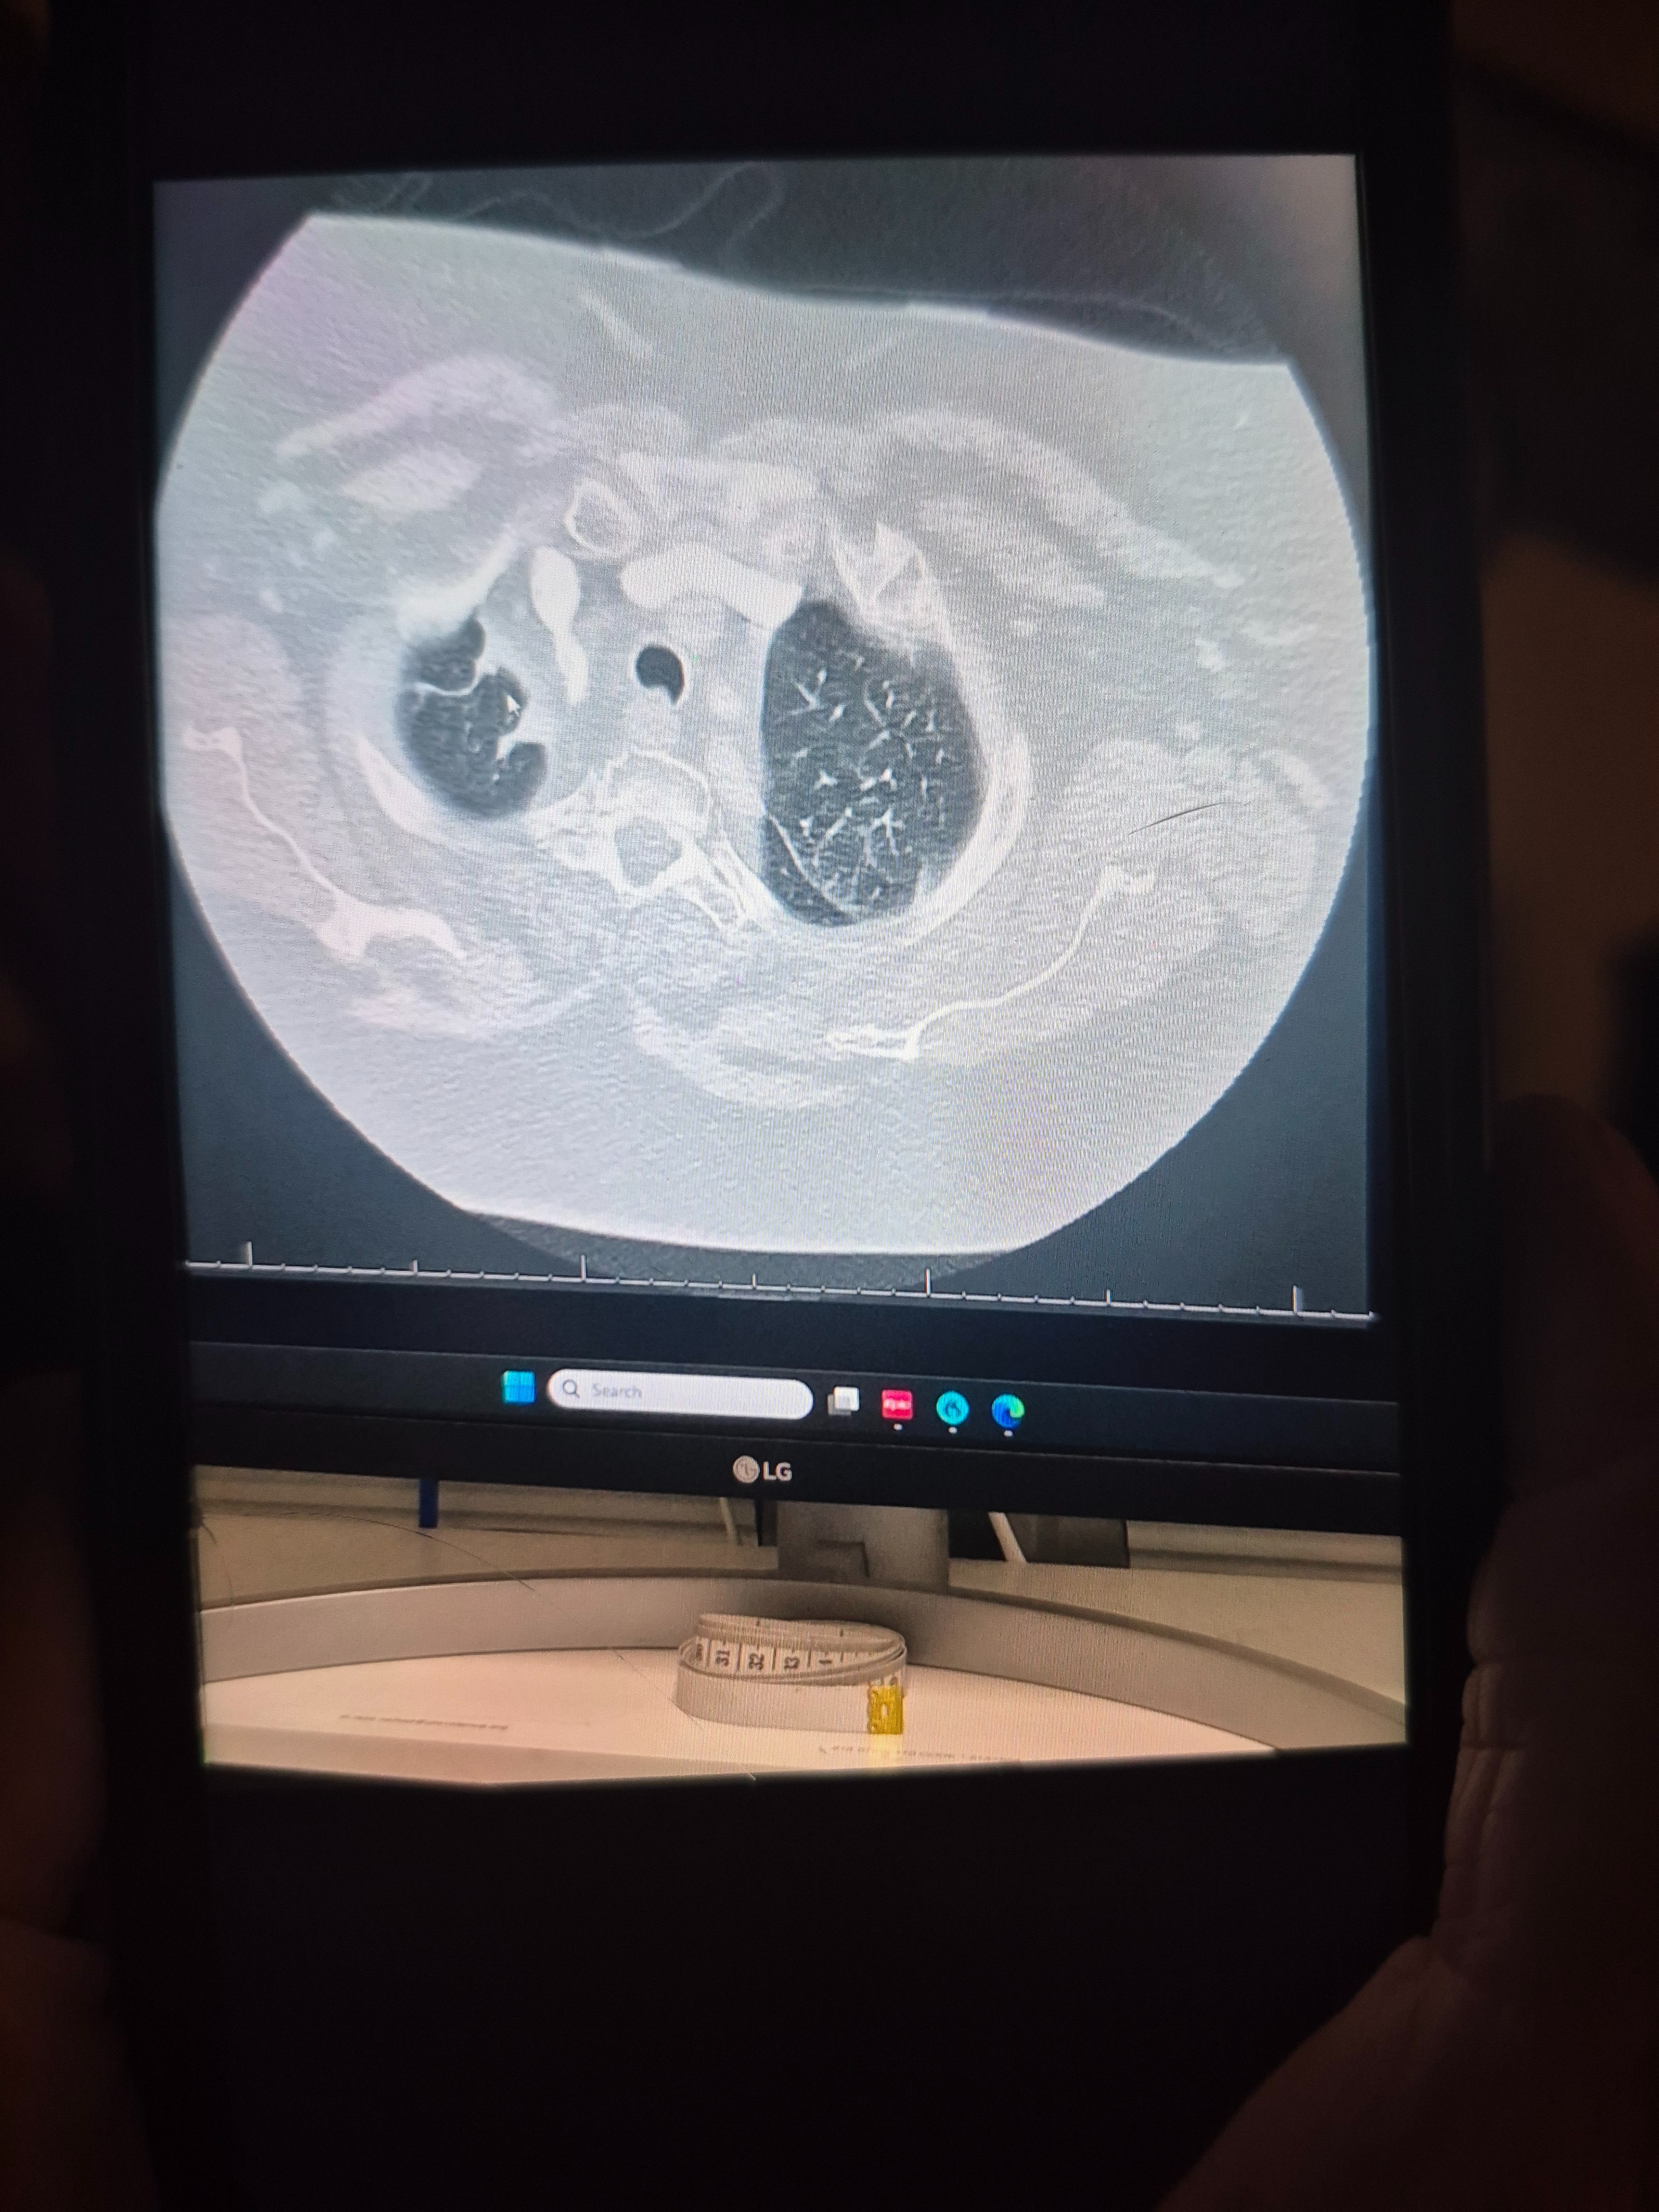

But instead of healing, the radiation caused devastating damage. A CT scan showed that both of my lungs were badly burned, leaving me with pulmonary fibrosis and chronic lung disease. I went from needing just 2 liters of oxygen to now relying on 5 liters daily—and my doctors tell me I will eventually need a lung transplant.